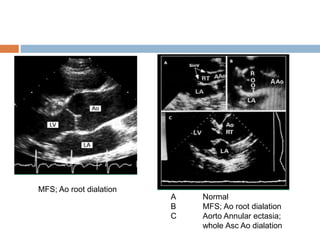

A Normal

B MFS; Ao root dialation

C Aorto Annular ectasia;

whole Asc Ao dialation

MFS; Ao root dialation

A Normal B MFS;Ao root dialation C Aorto Annular ectasia; whole Asc Ao dialation MFS; Ao root dialation